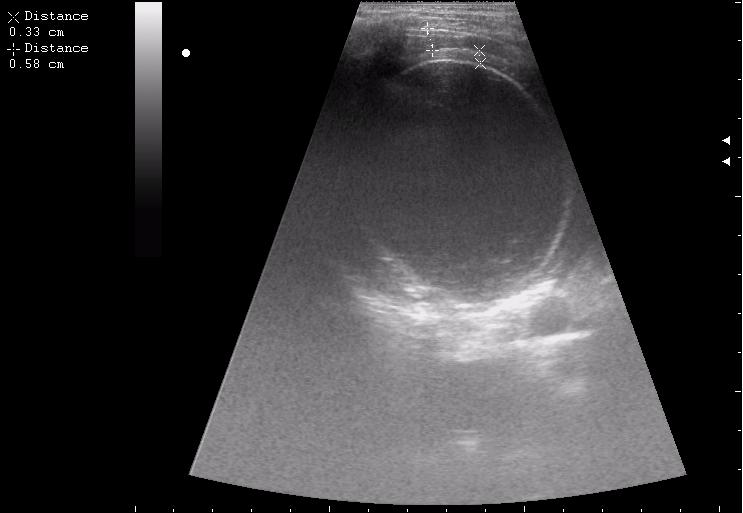

до операции